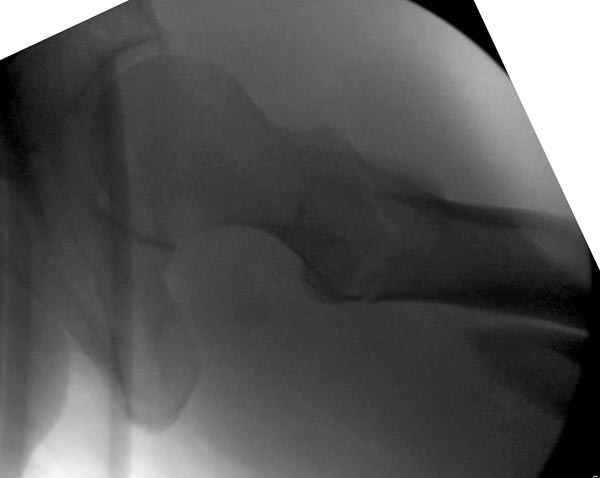

Как раз недавно у меня был примерный случай: больному 36 лет, поступил ночью, травма в результате мотоциклетной аварии, кроме чрезвертельного и спирального перелома левого бедра имеется переломы костей предплечья с этой же стороны. Скелетное вытяжение, а на следующий день больной про оперирован на ортопедическом столе с дистракцией. Чтобы не расколоть чрезвертельный перелом провели временную спицу ближе к переднему кортексу, из малого разреза костодержатель для репозиции, а фиксацию провели антиградным штифтом. Этапы операции на снимках.